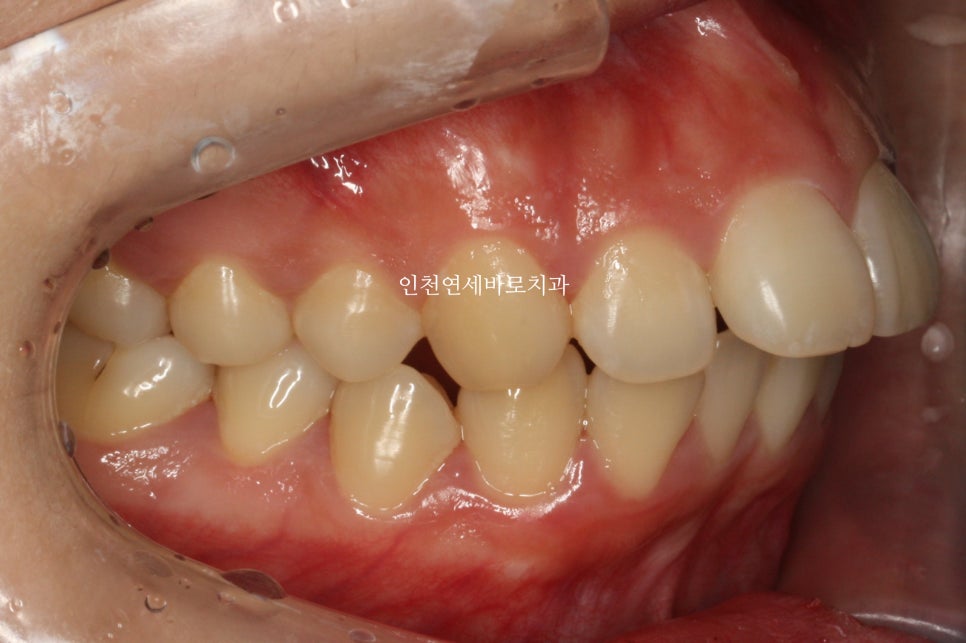

벌써 거의 5년전에 오셨던 환자분입니다

돌출을 해소 하고 싶어서 오신 분입니다.

치료방법은 발치를 동반한 미니스크류 교정치료입니다.